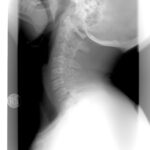

It is perfectly fine to take the medical route and wait to see the doctor. The doctor (who will just prescribe pills and maybe take pictures of the neck). You will be fine seeing a provider who will see you for 3 minutes (if you are lucky) and not even really look at your neck. It is not a big deal that you will be told those x-rays of your neck show you have the spine of a much older person (because that is was doctors like to do to scare patients into surgery). Don’t worry, you